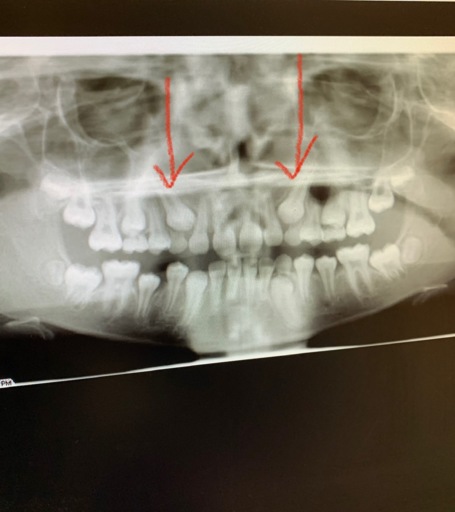

\\\"My son is 12 years old. He has two impact canines. Pulled his baby ones, put him in braces due to over crowding bottom and over bite. Now we need to make the hard decision to pull his adult lateral teeth to make room for the canine to come down. The oral surgent is suggesting this due to the position of the canine. I wish we can save them all, but he is saying it\\\'s a big surgery, it could cause damage to some roots of heathy teeth, and there\\\'s a good possibility they won\\\'t come down. The canines are lying vertical with the tips petruding between the front teeth and the lateral. He says by pulling the teeth they will easily come down with the least amount of surgery and the best outcome. What do you think? There\\\'s nothing like having your own teeth , but is the surgery worth the risk or should I just pull the laterals?